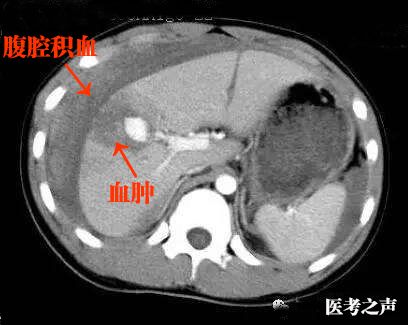

肝挫伤及包膜下血肿的ct表现